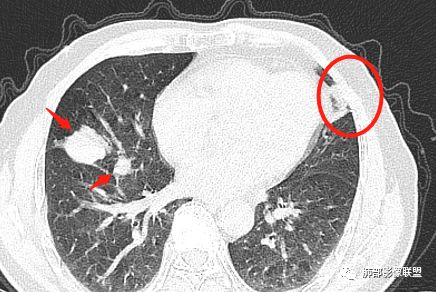

我来抛砖引玉:

空气储留,支气管炎

管辖的支气管是壁增厚,狭窄的

它不是只有一支支气管有问题,而是多支

这个是上叶支气管,而且一般慢性炎症更容易空气储留,因为是缓慢的才会气体易进难出。

主病灶在中叶,但是左肺舌段叶有条索影,陈旧病变。蓝色箭头支气管受压,是淋巴结肿大

主病灶在中叶,但是还有结节状病变在下叶

这个支气管是走形通畅,但是壁增厚的。比较符合炎症改变

下面我们看看支气管都在吗?

内侧段是通畅但是受压的

外侧段一开始狭窄

但是远端通畅,所以我认为支气管都没有堵塞,不太可能是鳞癌

边缘还有多发小灶

淋巴结肿大,钙化。

但是钙化,密度高,没有融合,平扫没有坏死

病灶明显平直,中央是粘液栓,低密度,分界清楚

综上,考虑炎症,结核。

吴婧老师和南边老师都对该病例进行了深入分析。从支气管管壁的增厚,支气管狭窄后扩张,支气管粘液栓,病灶形态,到病灶不均匀强化及坏死彻底,到周边病灶及肺组织空气的潴留,加之纵隔内淋巴结肿大伴钙化等等,都支持慢性炎性病灶,尤其是结核。

现在小编来增加一个炎性另一个征象,是我们王兆宇老师原创的----就是墨西哥仙人掌征。

墨西哥仙人掌征---结核        影像上结核灶,粗大的均匀枝干,推测是支气管囊状扩张引起的,在非支气管区,形成圆形坏死囊群;如果这些坏死比较稀薄,又遇到扩张支气管,就会形成粗大的“墨西哥仙人掌”。结核引起的支气管近端炎症纤维化,可以造成支气管阻塞,从而将干酪样坏死物封堵在管腔内。仙人掌主干内部应该是干酪为主,稀薄的,具有流动性,时间久了会出现钙化。

结核坏死与鳞癌鉴别有一点是结核坏死没有方向性,鳞癌有。鳞癌靠近支气管近端部分,血供容易维持,不易坏死,所以坏死靠外侧。而结核干酪样坏死,把一定体积的流动性坏死物,包裹起来,什么形状最省料?坏死物包裹,表面积最省的自然是圆球形,而遇到支气管,坏死物一多,就把支气管撑大了。包裹物是就地取材,扩张的支气管就成了包裹结构。